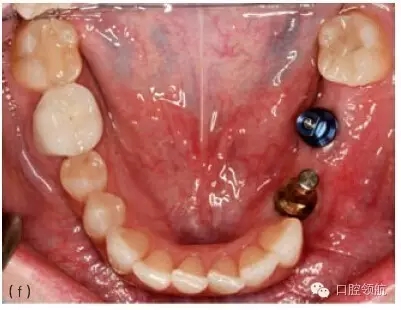

圖10.1 (a)個性化基臺連接在種植體上的牙合面觀。螺絲的長軸對應的是種植體的長軸,螺絲的長軸傾斜,基臺螺絲孔通頰側(cè)面。(b)成品基臺的頰面觀,螺絲的入口清晰可見。(c)上頜種植體的轉(zhuǎn)移替代體,反映種植體頰側(cè)傾斜的角度。(d)使用個性化鑄造基臺能獲得良好的美學效果。(e)轉(zhuǎn)移替代體顯示種植體的方向不平衡。(f)轉(zhuǎn)移替代體在口內(nèi)頜面觀,如圖可見遠中種植體舌傾。(g)制作診斷蠟型以確定最終修復體的外形。(h)個性化基臺的代型,遠中種植體的螺絲入口位于近中舌側(cè)位。固定局部義齒將會粘結(jié)于個性化基臺上。

圖10.4 (a)在頜骨模型上,環(huán)鉆置于種植體上。環(huán)鉆是空心柱狀的,鉆的末端有切割螺紋。它放在種植體上,可以順著種植體邊緣周的骨組織的切線方向環(huán)行去除骨組織,從而使種植體移除造成的創(chuàng)傷減到最小。(b)種植單冠的頰面觀,種植修復后患者產(chǎn)生持續(xù)性的疼痛,且無法緩解,需要取出種植體。(c)根尖片顯示種植體正常。(d) 取出牙冠,翻瓣暴

露種植體。(e)用環(huán)形鉆取出包繞種植體的骨環(huán)。(f)環(huán)形鉆包繞種植體,環(huán)形切削達種植體全長。(g)環(huán)形鉆切削完畢,(環(huán)形鉆中心的)切除的骨組織包繞種植體,種植體周圍已被分離,只有根尖區(qū)還有骨組織與種植體相連接。將使用一種器械,置于骨環(huán)周,切斷根尖區(qū)的骨組織。(h)包含種植體在內(nèi)的骨環(huán)被取出。(i)取出后置于外科盤上,可見種植體及附著周圍薄層的骨組織。種植體植入時曾植骨,種植體周可見殘留的顆粒狀的骨移植材料。(j)種植體移除后,去骨創(chuàng)面的牙合面觀。(k)將骨移植材料(同種異體骨與異種骨移植材料混合)放置在去骨創(chuàng)面中。(l)放上屏障膜,用釘固定。